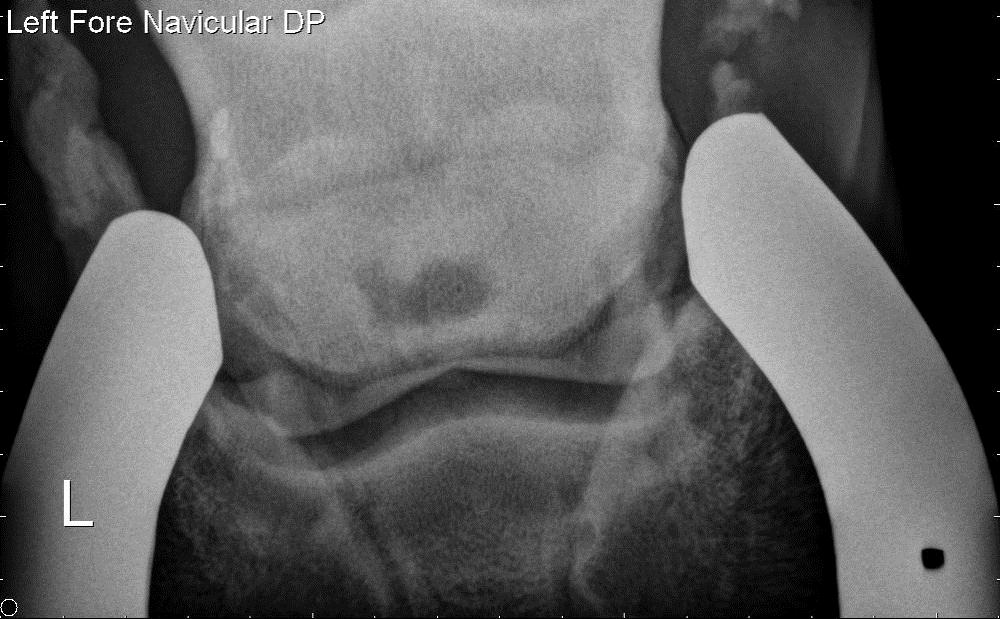

As recommended by the examining veterinarian (me), the front feet were radiographed with plans to radiograph the hocks as well. However, a large cyst was identified in the left navicular bone.

Compared to the right navicular bone (image below), an irregularly shaped lucency (dark circle) is present in the center of the navicular bone (image above). Although the gelding was not lame, the exam was stopped and the horse was FAILED for sale and intended use. Everyone involved (including myself) were very surprised with the radiographic findings. However, navicular bone cysts are significant findings and will likely result in poor performance and lameness at some point in the future. As I tell my clients, my crystal ball is "cloudy" at best; however these findings are considered a deal breaker.